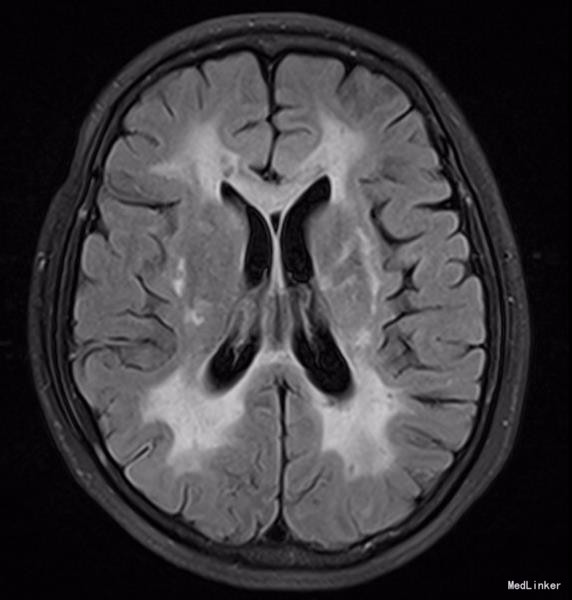

神清,说话吐词清晰。双侧瞳孔等大等圆,眼球运动正常,光反射灵敏,无面舌瘫,颈软。左手握力下降,右下肢轻瘫试验阳性,双上肢腱反射稍高,双侧膝反射亢进,霍夫曼征及内罗里索征阳性。直线行走试验阳性,闭目难立征阴性,双侧指鼻试验阴性。双侧病理征未引出,四肢浅感觉等称。实验室检查未见明显异常。MRI示:脑干、双侧颞极、外囊、额顶叶、放射冠区及丘脑、脑桥异常信号,结合MRS提示符合缺血性改变,部分软化灶形成.结合病变位置(颞极、外囊)及患者年龄,考虑CADASIL可能。头颈血管大致正常,NOTCH3基因见图